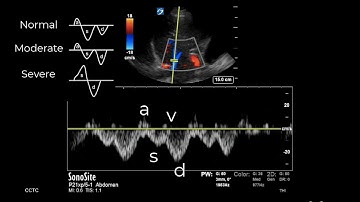

Doppler Flow Waveforms: Triphasic, Biphasic, Monophasic